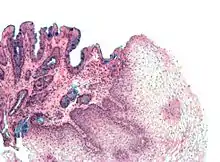

The mucosal layer consists of a epithelial layer, and its underlying supportive tissue, the Lamina Propria. It is separated from the submucosal layer by the Muscularis Mucosa. The epithelial layer varies from section to section of the gut. In the oesophagus it is a non-cornified stratified squamous epithelium; in the stomach it is mainly mucosal cells; the small intestine and large intestine are characterized by absorptive cells, with many mucous producing goblet cells. In the absorptive sections of the intestine, the surface are for absorption is greatly increased by finger-like projections into the lumen called villi, and the absorptive cells themselves also have small projections of microvilli, giving them the appearence of a brush border when viewed with a light microscope.

The surface for absorption is increased in many ways: the mucosa of the small intestine is thrown into folds called rugae; the mucosa itself has numerous finger-like projections called villi, and the epithelial cells are also covered with numerous projections called microvilli. The microvilli give the appearance of a 'brush' on light microscopy; hence the term brush border. The following illustration shows the anatomy of a villi:

Mucous is secreted by numerous goblet cells; other cells are specialized for absorption and are known as absorptive cells. In the base of the crypts are numerous secretory cells which secrete the digestive enzymes of the small intestine. Some of the crypts penetrate into the submucosal layer, forming digestive glands which will communicate with the mucosa via a secretory duct.

Epithelial Regeneration

Epithelial cells have a lifetime of 5–7 days. New cells are continuously being generated in the crypts, and migrate up the sides of the villi. These cells differentiate into either goblet cells (10–25%) or absorptive cells. Old cells are shed from the tips of the villi, migrating upwards and forming new villi.